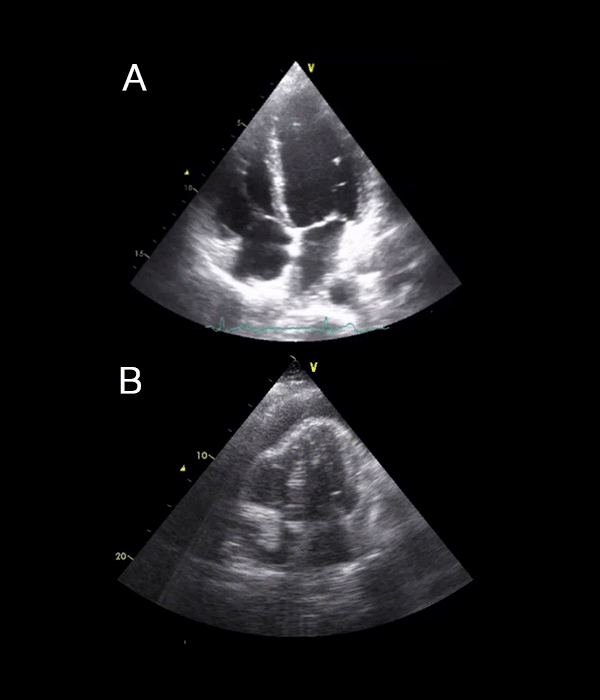

22 Pericardial fluid collection examples USabcd What Is Pericardial Fluid In Medical Terms pericardial effusion is the medical term for fluid buildup in the space around the heart. It can happen for many reasons, like infections, injuries or. Your healthcare provider may use specific techniques, tests, or imaging to make a diagnosis. Treatment can depend on what is causing the fluid to build up. There are various possible causes for this condition.. What Is Pericardial Fluid In Medical Terms.

Focused Assessment with Sonography in Trauma Pericardial Fluid What Is Pericardial Fluid In Medical Terms There are various possible causes for this condition. If left untreated, it can impact heart function. a pericardial effusion is excess fluid between your heart and the sac (pericardium) surrounding your heart. excess fluid around the heart is known as a pericardial effusion. pericardial effusion is when the sac around the heart, called the pericardium, fills with. What Is Pericardial Fluid In Medical Terms.